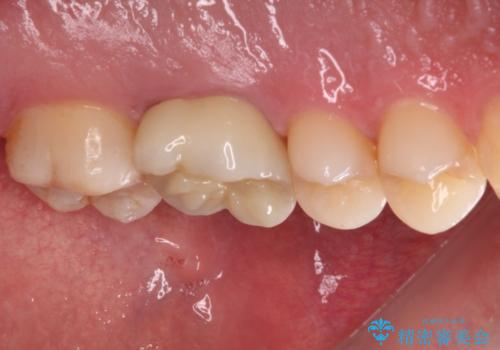

- 鼻づまりがひどく耳鼻科を受診したところ、虫歯が原因の可能性があるとのことで来院された患者様です。

レントゲン写真では根尖部に病変があるように見えたため、神経が失活しているのかチェックをしたところ、生活反応はありませんでした。

根管治療を行い、症状の経過を見て、セラミッククラウンにて補綴治療を行うこととしました。